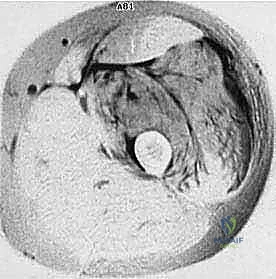

المرحلة الأولى: استئصال الورم (Resection)

يتم فتح الجلد والأنسجة بعناية فائقة. التحدي الأكبر هنا هو فصل الورم عن الأوعية الدموية والأعصاب الرئيسية المغذية للطرف. يستخدم الدكتور هطيف تقنيات الجراحة الميكروسكوبية لضمان سلامة هذه الهياكل الحيوية، مما يحافظ على حيوية الطرف وحركته.

- مناظير المفاصل 4K: في حالات تشخيص أورام المفاصل أو أخذ العينات، توفر هذه التقنية رؤية فائقة الدقة لتجنب نشر الخلايا السرطانية.

- الجراحة الميكروسكوبية (Microsurgery): لخياطة الأوعية الدموية والأعصاب الدقيقة التي لا تُرى بالعين المجردة، مما يضمن تدفق الدم للطرف بعد الاستئصال الواسع.